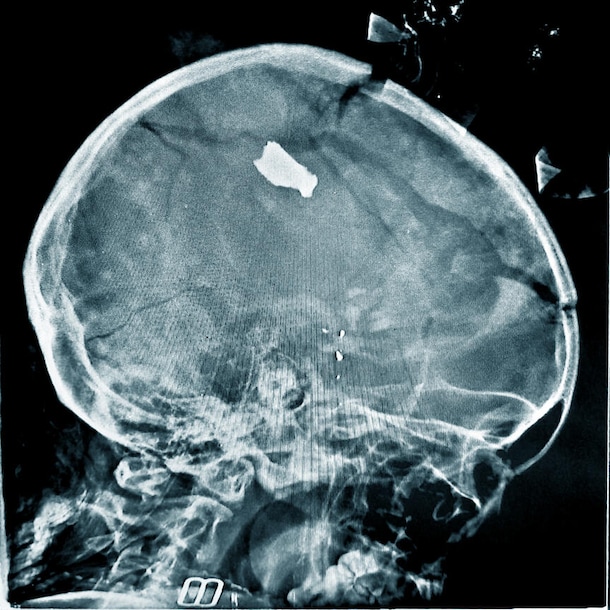

Eén slachtoffer, een meisje van slechts 20 maanden, had granaatscherven in haar hoofd. Dat zie je in de afbeelding hieronder:

Een van de artsen vertelt aan de hulporganisatie dat 'dit soort gevallen' veel voorkomen. "Gelukkig heeft dit meisje het overleefd", zegt de arts, "anderen hadden minder geluk."